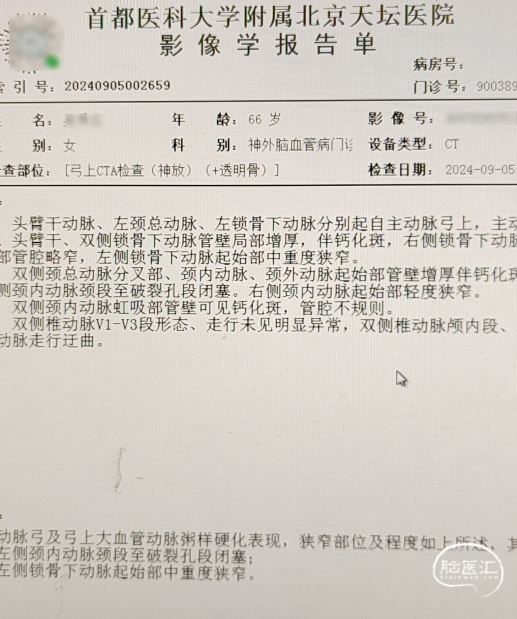

· 于我院查颈部血管超声示“双侧颈动脉内-中膜增厚伴多发斑块形成;左侧颈内动脉闭塞可能,建议超声造影;左侧颈外动脉起始处狭窄,狭窄率70-99%;右侧锁骨下动脉起始处斑块形成”。查头颈部血管CTA示“主动脉弓及弓上大血管动脉粥样硬化表现,左侧颈内动脉颈段至破裂孔段闭塞;左侧锁骨下动脉起始部中重度狭窄”。

头颈部CTA影像及报告(2024-07-24)。

入院头颈部CTA影像及报告(2024-09-05)。